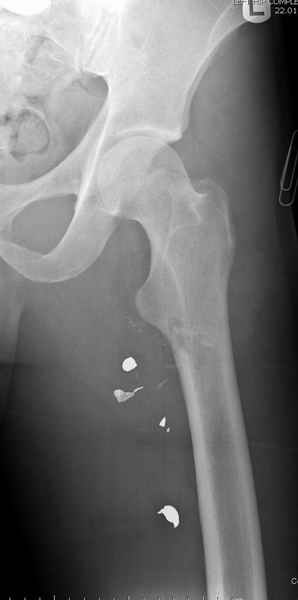

Больной с огнестрельным переломом бедра с вовлечением около 15% медиального кортекса, входное отверстие около 1 см в диаметре; стабильный, без сосудистых и неврологических признаков.

Учитывая, что больной получил травму не во время визита в церковь, и он является одним из представителем 40 миллионного “outstanding itizen”, без медицинской страховки, без работы в свои 39 лет, и без надлежающей ортопедической дисциплины у которого отсутсвует страх стрессового перелома, было рекомендовано оперативное лечение: профилактическое антеградное интрамедуллярное штифтование.

Выглядит агрессивно, и обычно госпиталь, беря финансовые расходы, остается в убытке, но мы всё же посчитали, что издержки от штифтования намного меньше, чем возможные финансовые и моральные издержки лечения таких больных, но с осложнением.

Методика штифтования при отсутствии большой зоны перелома как при онкологических профилактических штифтованиях, расверливание интрамедуллярного канала проводим с предварительным наложением дополнительного дренажного отверстия в дистальном отделе бедра (в данном случаи в канале оставили 6.5 мм канюлированный шуруп), иначе при создании давления в канале во время сверления имеется опасность эмболизации легочной артерии тромбом.